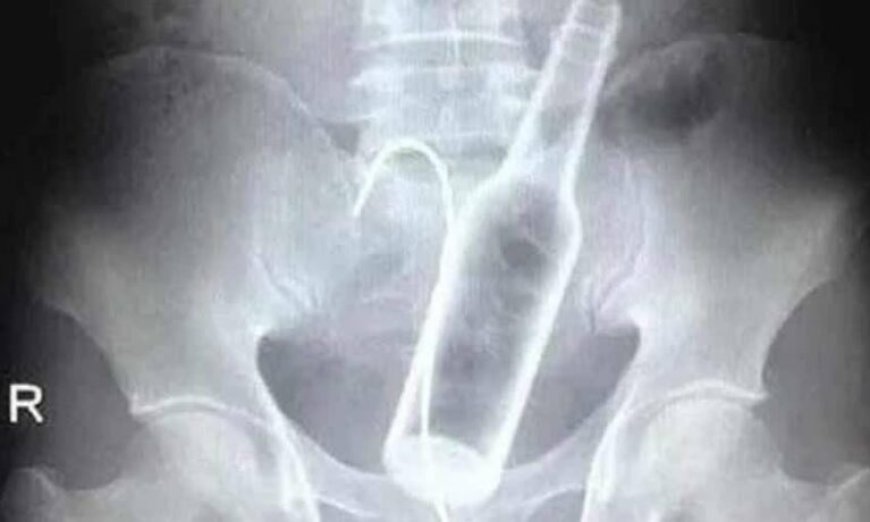

Um homem precisou ser submetido a uma cirurgia de emergência na Santa Casa de Poços de Caldas, em Minas Gerais, após dar entrada no hospital com duas garrafas introduzidas no ânus. O caso ocorreu no último dia 29 de setembro e chamou a atenção da equipe médica pela gravidade e pela complexidade do procedimento.

De acordo com informações divulgadas pelo portal Onda Poços, os profissionais de saúde tentaram remover os objetos manualmente, mas não tiveram sucesso. Isso porque uma das garrafas — uma de vidro e outra de plástico — havia se deslocado para uma parte mais alta do intestino, o que impediu a retirada por métodos menos invasivos.

Diante da situação, o paciente precisou passar por uma laparotomia, cirurgia abdominal que permite o acesso direto aos órgãos internos. Durante o procedimento, os médicos conseguiram retirar as duas garrafas com segurança.